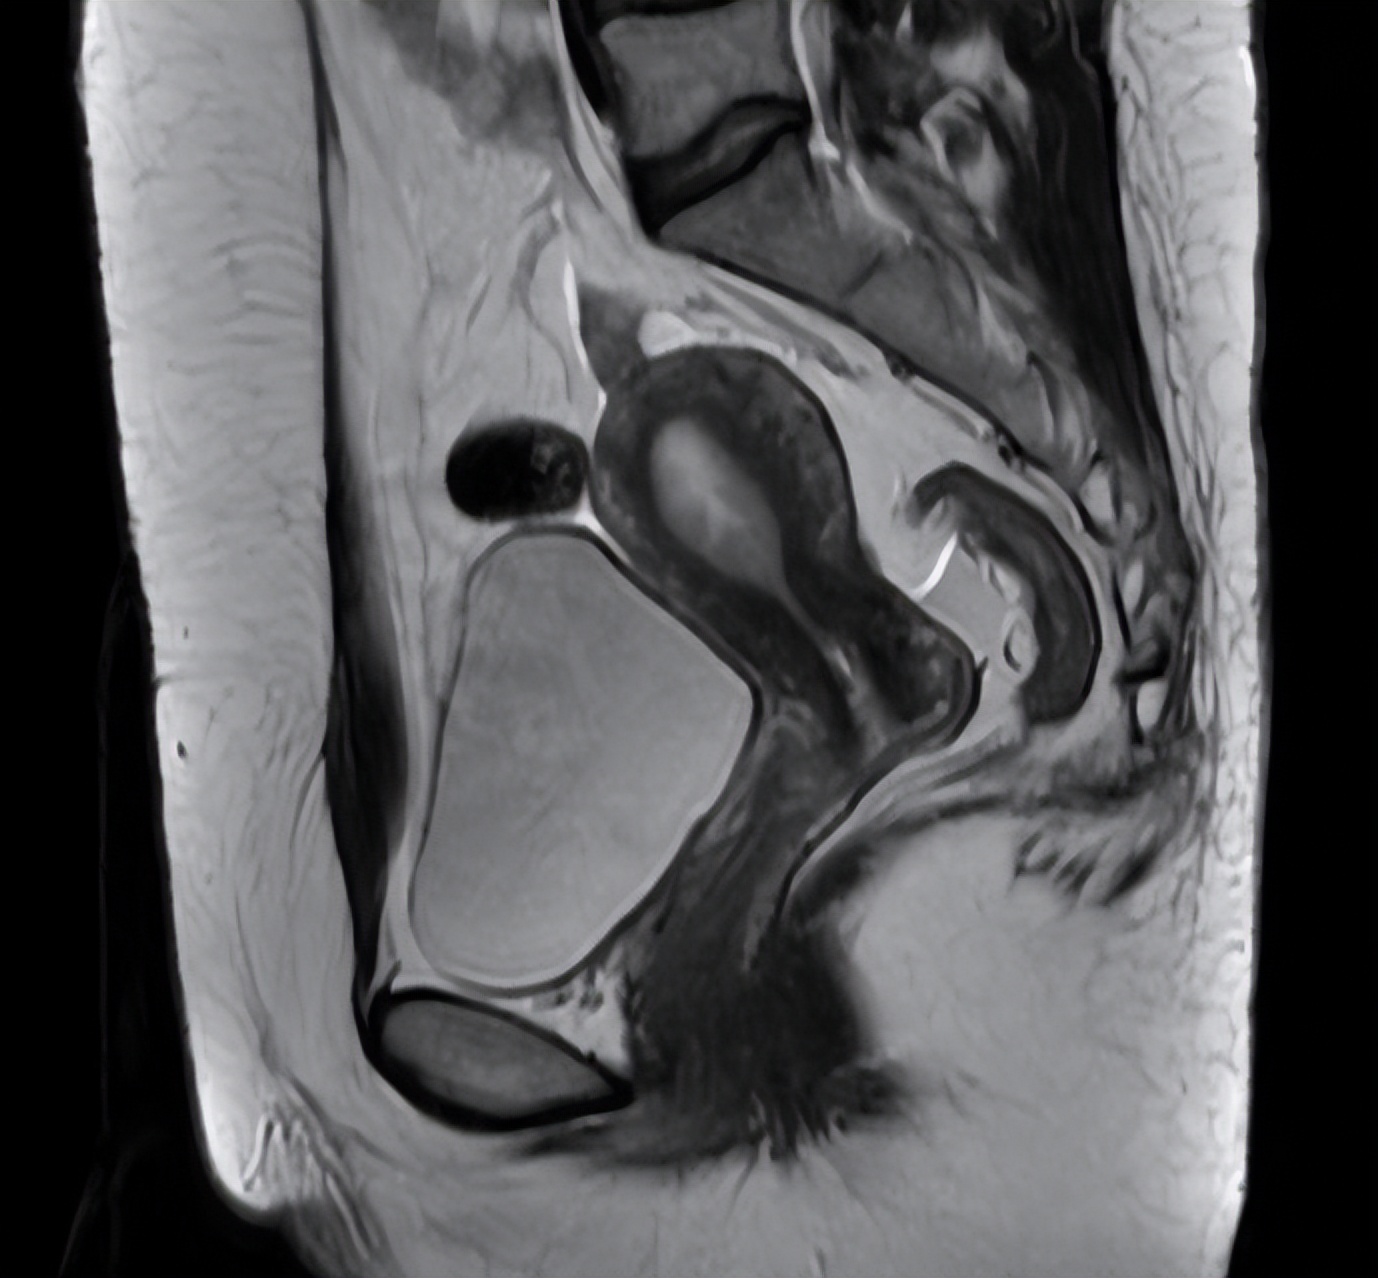

患者的病理会诊结果与外院一致,盆腔核磁提示宫颈占位1.6*1.3*1.1cm,肿瘤标记物CA 199:87.6U/ml。结合门诊查体,考虑诊断宫颈腺癌IB1期,在治疗方案上,患者为年轻女性,手术治疗较放化疗能更好的保留阴道功能。

图片来源 :讲述者提供

再次见面是术后两周,患者已经拔除了尿管,排尿后行超声检查提示残余尿正常。术后病理为病变符合宫颈腺癌(HPV相关型,病灶水平最大径1.8cm,浸润深度0.4cm),无其他位置受累。因此患者后续无需补充其他治疗,可定期随诊。